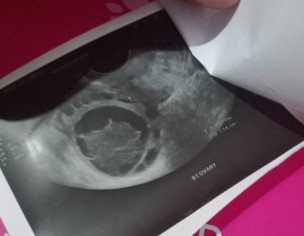

I had miscarriage its been 17 days continously bleeding and very painful. Had ultrasound done. Please check my reports and tell me what's the problem?

Report is too dim to be read . Better to start Tab Breeky 1+1 ×3 days , hopefully it will help .